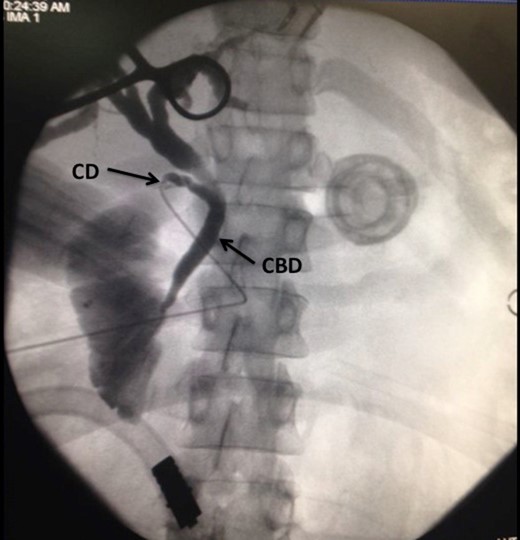

A laparoscopic completion cholecystectomy was performed. There were multiple dense adhesions that precluded visualization of the gallbladder remnant (Fig. 2). Meticulous dissection with cautery attached to ‘hot scissors’ eventually presented the gallbladder remnant (Fig. 3). Scarring at Calot's triangle prevented retrograde dissection, so the ‘dome down’ technique was used to identify cystic duct (CD) (Fig. 4) and right hepatic structures at the floor of an open-type Rouviere's sulcus (Fig. 5). Intraoperative cholangiography was performed via the CD using a 5Fr infant feeding (Fig. 6) and confirmed that: this structure was the CD, the extra-hepatic biliary tree was normal and there were no stones in the CBD (Fig. 7). At this point, the CD and artery were ligated and ‘hot scissors’ were used to separate the gallbladder remnant from the liver bed. This patient recovered uneventfully and remained asymptomatic 2 years later.

Choangiogram film demonstrating the catheter as it enters into the CD. A normal CBD is noted. There are no stones in the CBD and contrast is seen entering the duodenum.